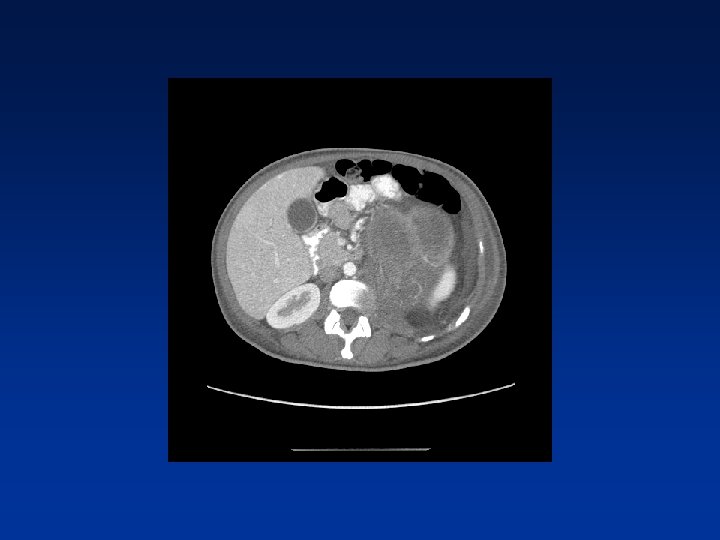

CASE